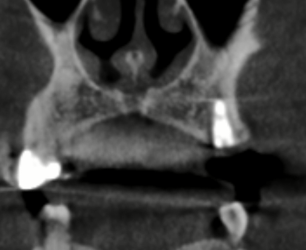

I do have more x rays that I’ll attach here.